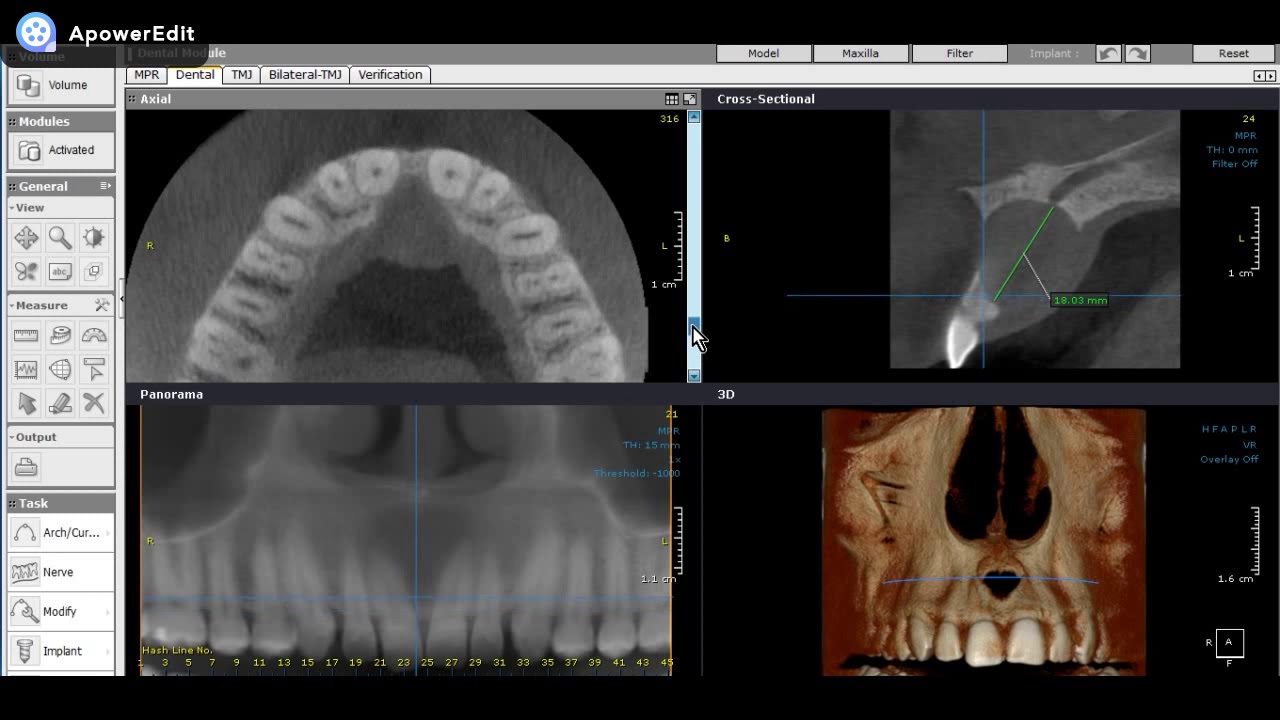

Exploramos o diagnóstico de uma lesão não odontogênica frequentemente encontrada na região anterior da maxila: o cisto do ducto nasopalatino. A análise detalhada da tomografia tridimensional revela uma área hipodensa que rompe a cortical do soalho da cavidade nasal e envolve o canal incisivo. Explicamos a importância de identificar essa condição, suas características prevalentes em homens entre 40 e 60 anos, e as melhores abordagens diagnósticas para os profissionais da odontologia. Se você é um profissional da área de radiologia odontológica, este vídeo oferece abordagens valiosas para o diagnóstico clínico.